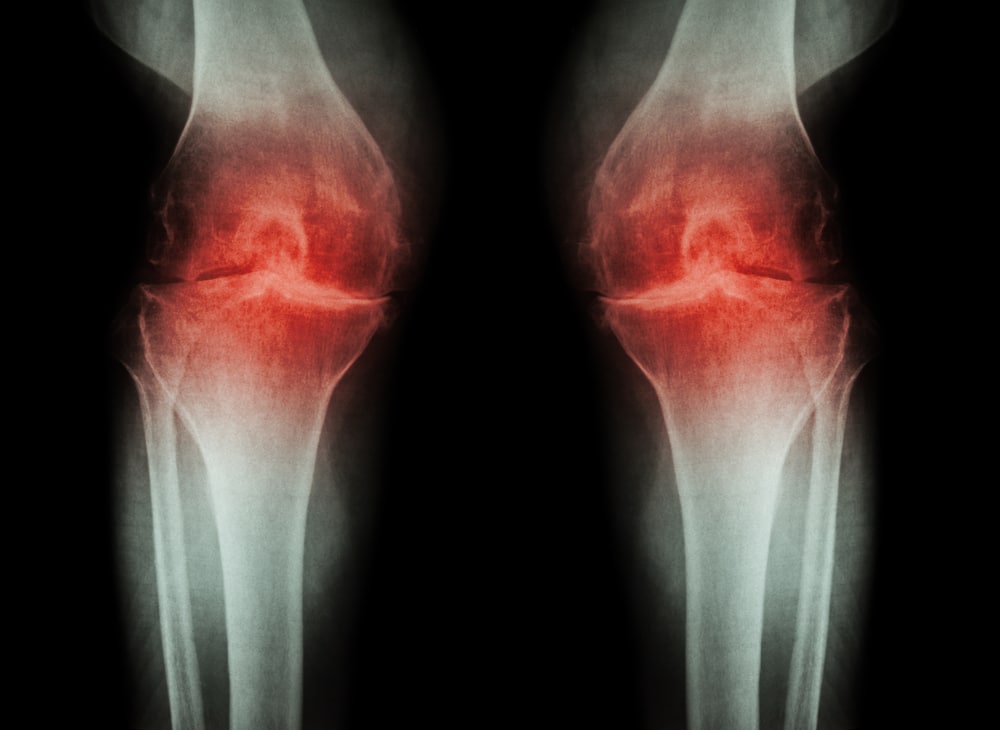

Arthritis In The Knee Cap . The diagnosis is restricted to arthritis seen only in this compartment of the knee. Knee arthritis occurs when the cushioning cartilage in the joint wears down, making the knee stiff and painful with certain movements. It develops where your patella (kneecap) makes contact with the end of your femur (upper leg bone) because. patellofemoral arthritis is a common cause of knee pain, especially in older adults. what you need to know. patellofemoral arthritis is diagnosed when there is significant loss of cartilage from the joint surface of the patella and the trochlea (the groove in the femur where the kneecap rests). arthritis of the knee cap, also called patellofemoral arthritis, is a common cause of pain at the front of the knee. Patellofemoral arthritis is a form of knee arthritis. learn about the causes, symptoms, and treatment of patellofemoral arthritis, a type of knee arthritis that affects the kneecap and the groove in the thighbone. It affects the joint where the kneecap meets the thighbone. The cartilage behind the knee. Find out how to prevent and manage pain, swelling, and stiffness in the front of your knee.

Xray Stages of Knee Arthritis YouTube Arthritis In The Knee Cap Patellofemoral arthritis is a form of knee arthritis. learn about the causes, symptoms, and treatment of patellofemoral arthritis, a type of knee arthritis that affects the kneecap and the groove in the thighbone. what you need to know. patellofemoral arthritis is diagnosed when there is significant loss of cartilage from the joint surface of the patella and. Arthritis In The Knee Cap.

Osteoarthritis of the Knee XRay Arthritis In The Knee Cap It affects the joint where the kneecap meets the thighbone. patellofemoral arthritis is diagnosed when there is significant loss of cartilage from the joint surface of the patella and the trochlea (the groove in the femur where the kneecap rests). what you need to know. It develops where your patella (kneecap) makes contact with the end of your. Arthritis In The Knee Cap.

Diagnosing Osteoarthritis with Knee Radiograph Sports Medicine Review Arthritis In The Knee Cap Patellofemoral arthritis is a form of knee arthritis. arthritis of the knee cap, also called patellofemoral arthritis, is a common cause of pain at the front of the knee. It develops where your patella (kneecap) makes contact with the end of your femur (upper leg bone) because. The cartilage behind the knee. Find out how to prevent and manage. Arthritis In The Knee Cap.

Medical xray knee joint image with arthritis ( Gout , Rheumatoid Arthritis In The Knee Cap It develops where your patella (kneecap) makes contact with the end of your femur (upper leg bone) because. arthritis of the knee cap, also called patellofemoral arthritis, is a common cause of pain at the front of the knee. Knee arthritis occurs when the cushioning cartilage in the joint wears down, making the knee stiff and painful with certain. Arthritis In The Knee Cap.